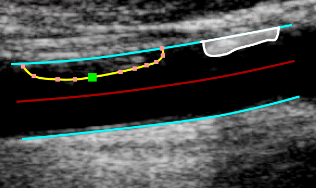

images/download/thumbnails/388694064/CVS_CAR_PlaquesBorders-version-1-modificationdate-1761817174877-api-v2.png

Modifica dei bordi

• Passare il mouse sul bordo da modificare.

• Cliccare e trascinare uno dei punti del bordo.